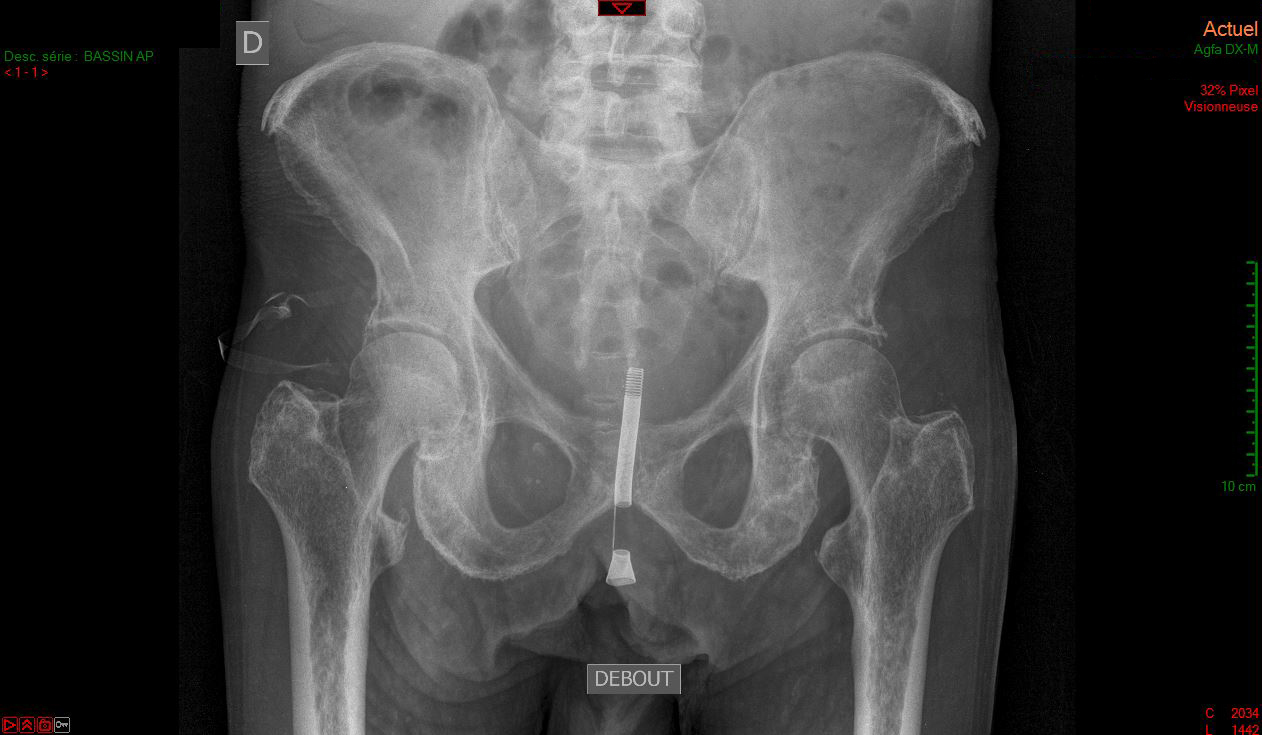

Quel est votre diagnostic ?

Il s'agit d'une prothèse de Fabian.